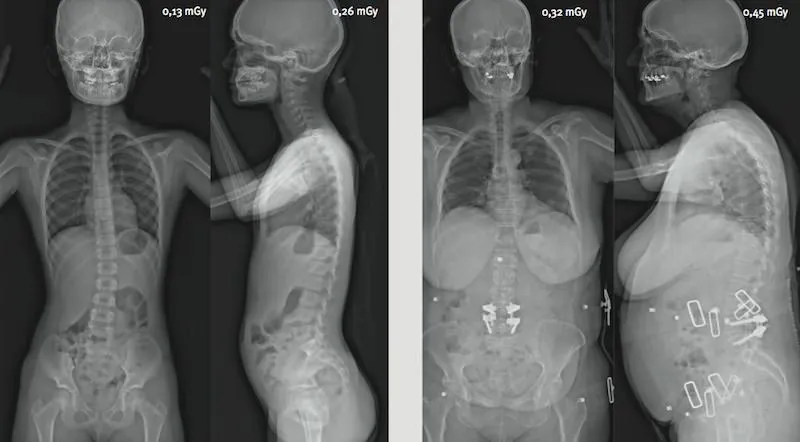

Diminution spectaculaire de l’irradiation

L’extrême sensibilité des détecteurs développés par Georges Charpak permet une acquisition corps entier, simultanée de face et de profil pour une dose 9 fois inférieure par rapport aux méthodes radiologiques classiques. La dose est jusqu’à 100 fois inférieure par rapport à un scanner.

Réduction de dose particulièrement importante pour les jeunes patients

La réduction d’irradiation est encore plus spectaculaire dans le cas des examens répétés comme les suivis de scoliose. De plus, ces suivis concernent bien souvent des patients très jeunes pour lesquels la réduction d’irradiation est encore plus bénéfique. L’analyse statique par EOS est fortement recommandée pour l’imagerie pédiatrique squelettique.

Dose d’irradiation comparée pour un examen corps entier face/profil

Dose comparée EOS / Scanner